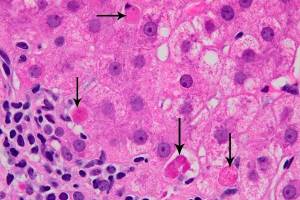

Цирроз печени – тяжелое хроническое заболевание, при котором функциональные клетки печени (гепатоциты) постепенно замещаются соединительной тканью, что приводит к уменьшению их общего количества.

К сожалению, в последнее время в гастроэнтерологической практике достаточно часто встречаются пациенты с фиброзом и циррозом печени.

Хронические вирусные гепатиты – группа инфекционных заболеваний, распространяющихся во всем мире с угрожающей скоростью.